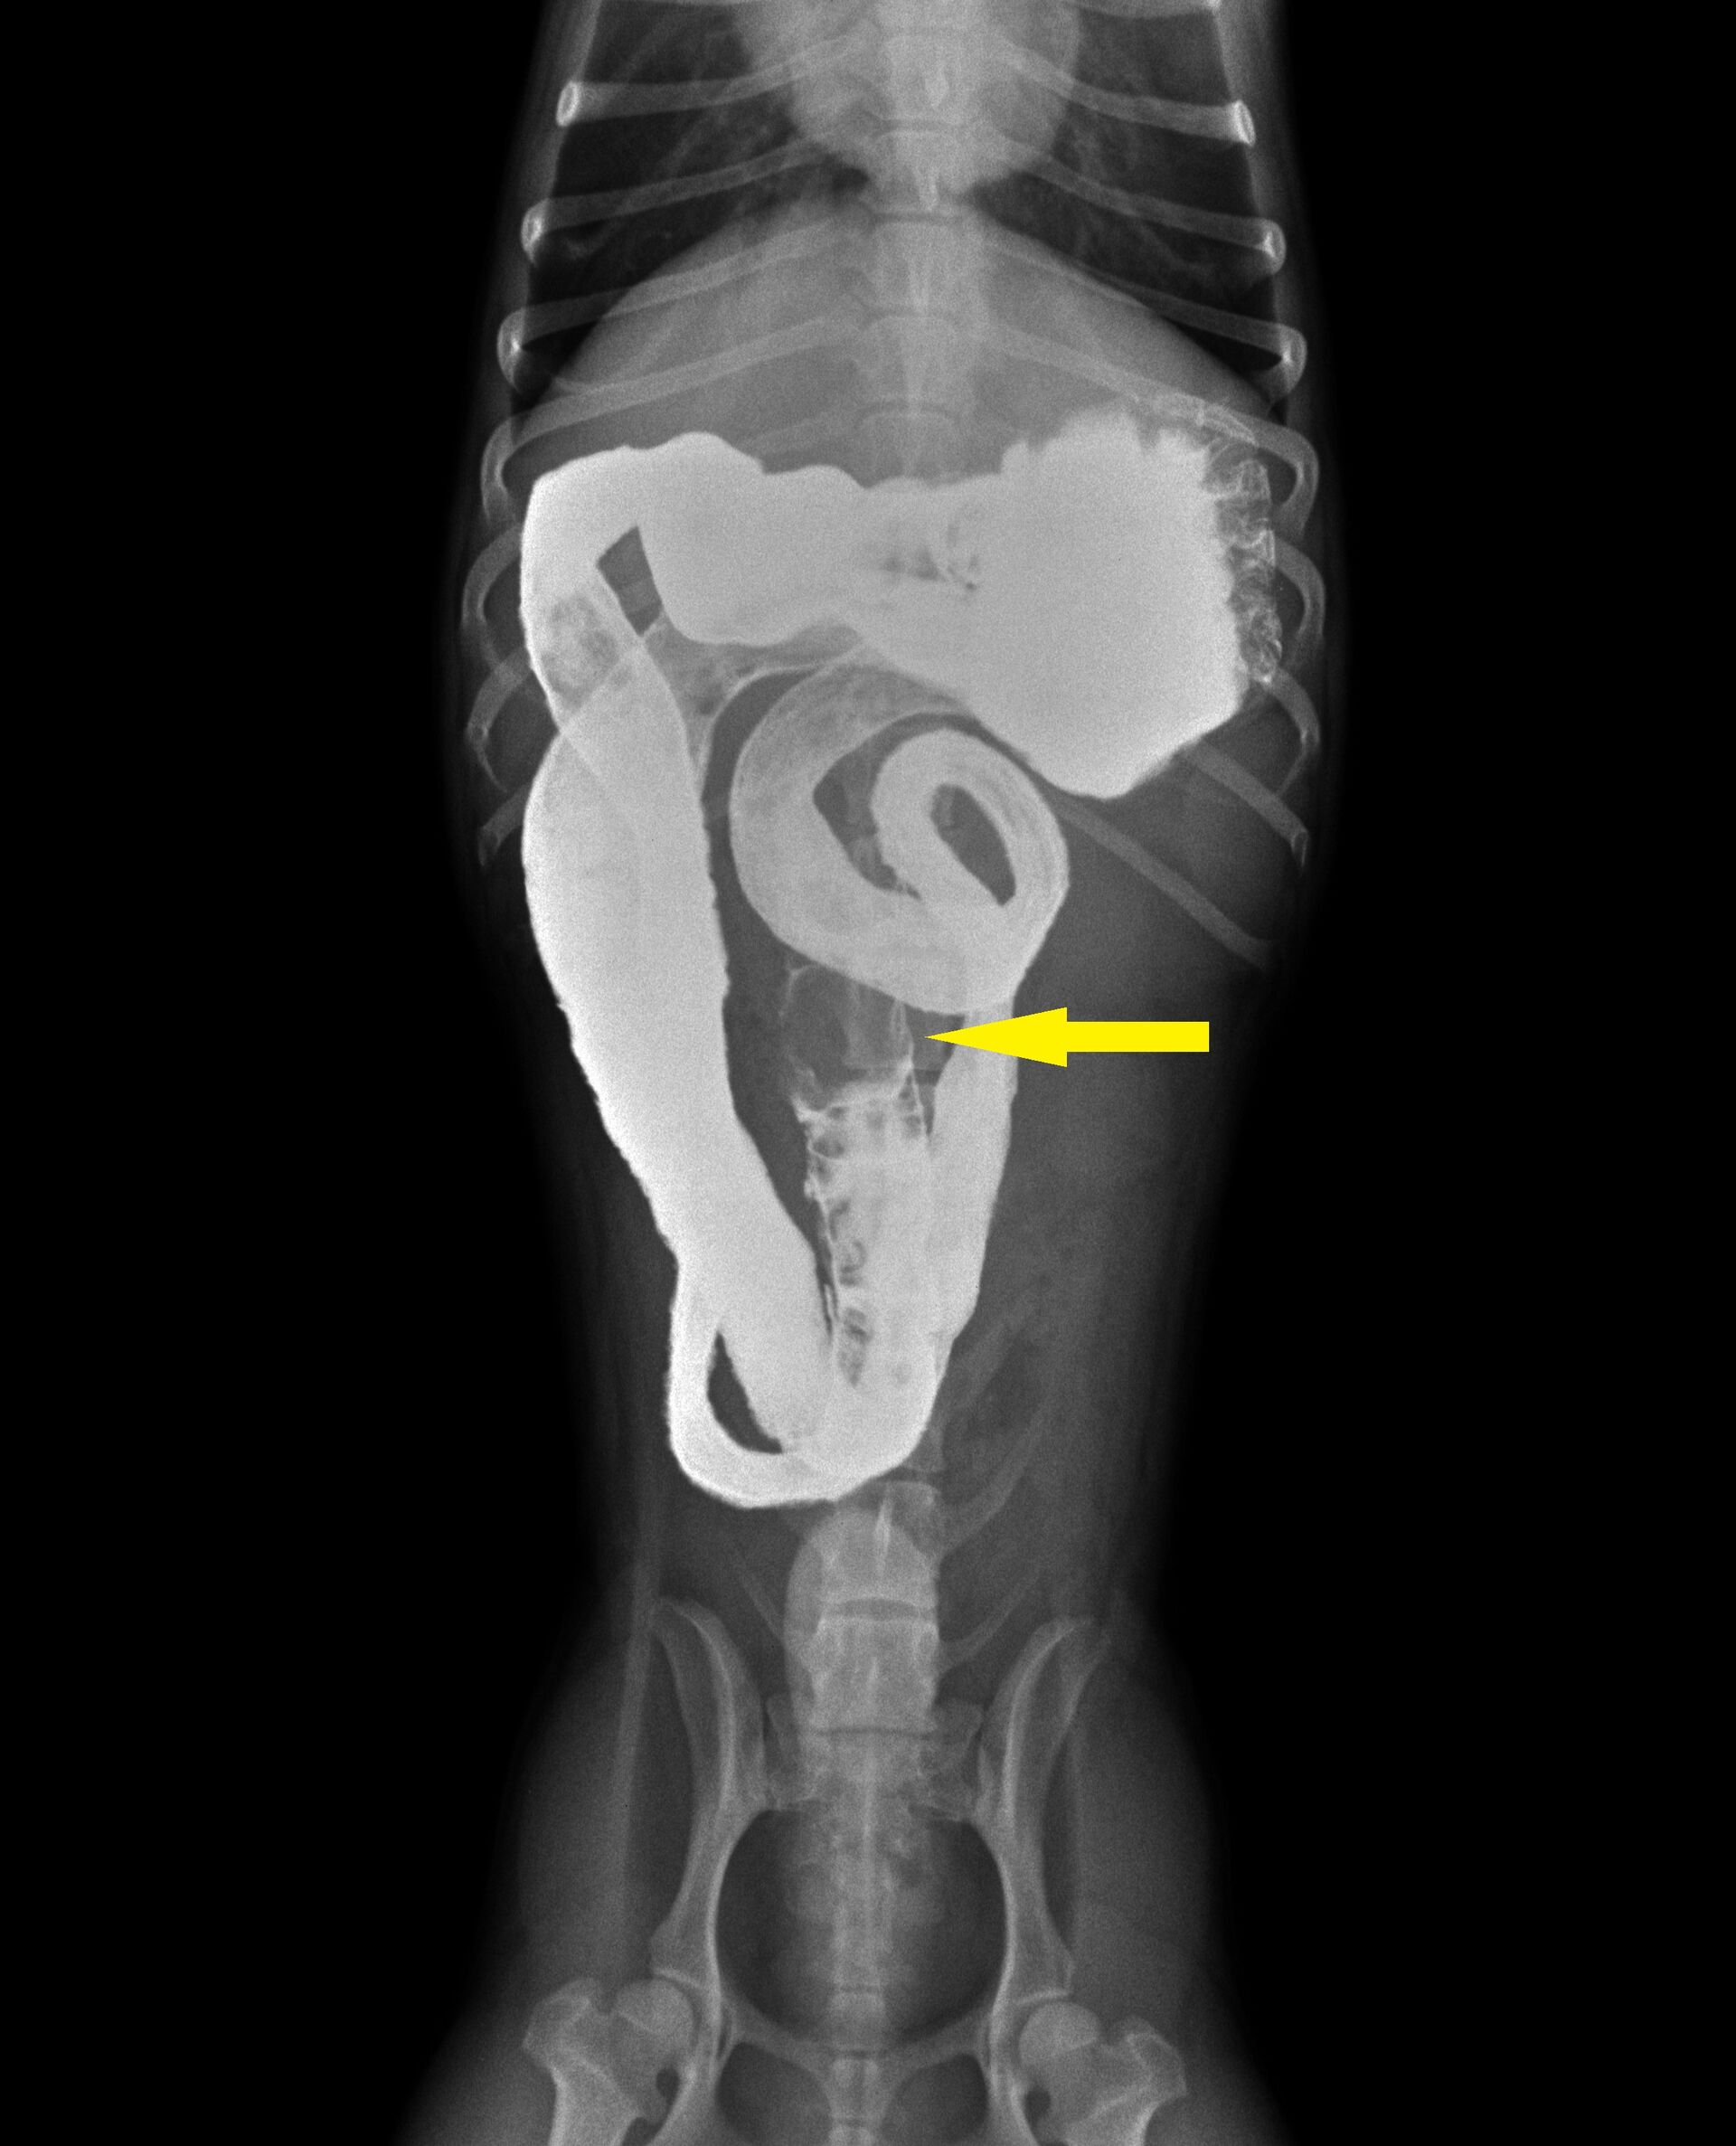

胃から十二指腸にかけて普通より少しガスが多く認められました。益々異物による腸閉塞が疑われたので、バリウム検査を行うことにしました。その結果が以下です。

黄色矢印のところでバリウムが止まって円形の異物のようなものが認められました。その後もバリウム投与後2時間までレントゲンを撮影しましたが、矢印のところからは全く進みませんでした。異物によって腸閉塞していることは疑いがありませんでしたので、手術を行いました。下の写真のように小腸内に異物が認められ、腸を切開し、異物を取り除きました。飼い主さんにお見せしたところ、いつも遊んでいるおもちゃの突起物であることがわかりました。